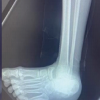

The radiological assessment (Fig. 3) demonstrated a medial peritalar dislocation of the left foot and an avulsion-fracture of the base of the 5th metatarsal in zone I.